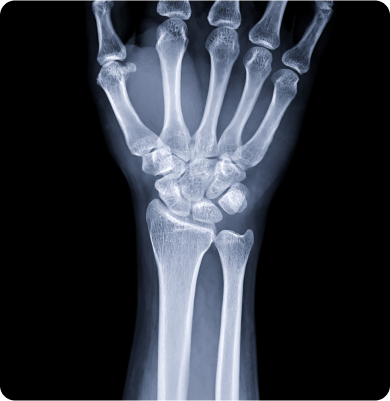

손목터널증후군

손목의 신경이 압박을 받아 발생하는 질환

주요원인

반복적인 손목 움직임이나 과도한 압박, 장시간의 손목 사용 등이 주요 원인으로 특히 컴퓨터 작업이나 스마트폰 사용 등에서 발생할 수 있습니다.

주요증상

• 손목이나 손끝에 저림이나 쑤시는 통증이 나타납니다.

• 손의 감각이 둔해지고 물건을 쥐기 어려운 증상이 발생합니다.

• 손목이나 손의 약화가 느껴지며 일상적인 작업을 하는 데 불편함을 겪을 수 있습니다.